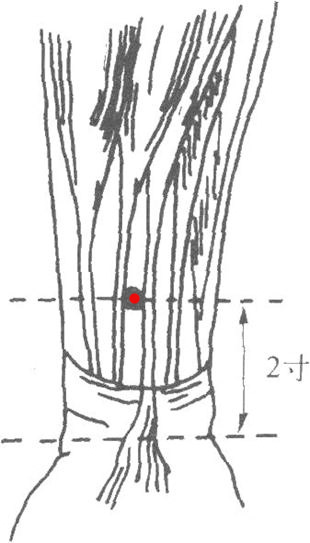

4.6 內關穴的定位

標準定位:內關穴在前臂掌側,當曲澤與大陵的連線上,腕橫紋上2寸,掌長肌腱與橈側腕屈肌腱之間[11]。

內關穴位於前臂掌側,腕橫紋上2寸,當掌長肌腱與橈側腕屈肌腱之間[12]。

內關穴位於前臂前區,腕掌側遠端橫紋上2寸,掌長肌腱與橈側腕屈肌腱之間。仰掌取穴。[12]

內關穴在前臂的位置

內關穴在前臂的位置

4.7 內關穴的取法

內關穴位於前臂前區,腕掌側遠端橫紋上2寸,掌長肌腱與橈側腕屈肌腱之間。仰掌取穴[12]。

握拳,手外展,微屈肘時,顯現兩肌肌腱[13]。伸臂仰掌,於掌後第一橫紋正中大陵直上2寸,當掌長肌肌腱與橈側腕屈肌肌腱之間處取穴[13]。若兩手的一側或雙側摸不到掌長肌肌腱,則以橈側腕屈肌肌腱尺側定位[13]。